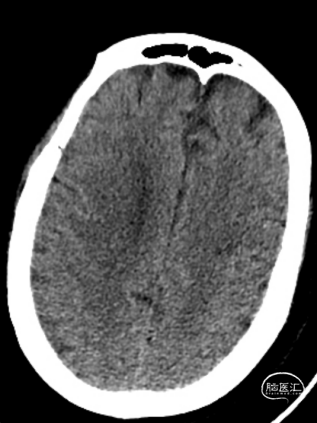

患者为急性脑梗死,头颅CT未见明显低密度病灶,CTA提示:右侧颈内动脉及右侧大脑中动脉M1段闭塞,远端分支减少,显影浅淡。目前患者神经功能缺损严重,有急诊取栓手术指征。

造影显示RICA:C1段起始部闭塞,残端呈锥形,TICI分级0级;RMCA未显影,远端由RACA经皮层支少量代偿,ASITN分级1-2级。

术后第一天复查颅脑CT未见异常染色及大面低密度病灶。

查头颅MRI:右侧基底节区、右侧顶颞岛叶急性脑梗死。